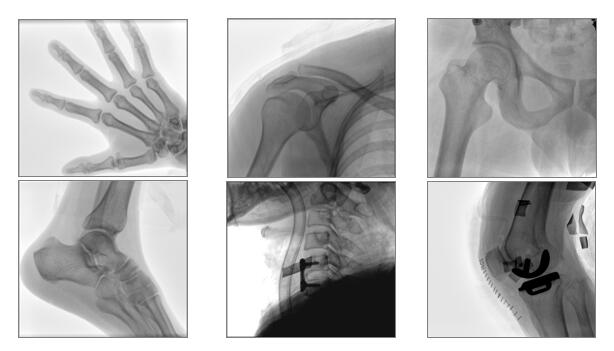

【產品臨床圖片】